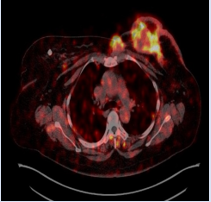

Baseline [18F] F-FDG PET -CT scan was done in the light of confirmed biopsy to assess locoregional nodal and distant metastasis. The study demonstrated increased FDG uptake in the left breast mass with skin, posterior chest wall involvement, multiple small satellite lesions, bilateral axillary and retropectoral lymph nodes (Figure 1 and 2).

Figure 2: FDG PET-CT fusion axial projection showed intense FDG uptake in the left breast mass, a satellite mass abutting the sternum and retropectoral lymph node.